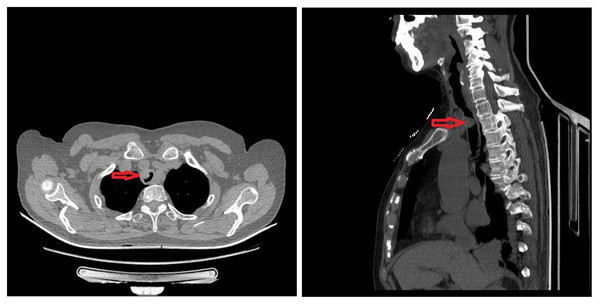

71岁的女性患者王某,因“胸闷气短1月余”于2020年08月31日入住我院胸外科。胸部CT及支气管三维重建提示主气道肿物(图1),气管镜检查提示距声门6cm、隆突上5cm处隆起性病变,位于胸锁关节后方,占据管腔60%,取病理活检提示“粘膜腺样囊性癌”(图2)。经过术前检查排除手术禁忌后李少民主任邀请急诊科、麻醉科等相关科室进行多学科会诊,遂决定行在ECMO配合喉罩通气下行气管肿瘤切除、气管吻合术。9月9日上午,患者进行全身麻醉后,急诊科团队立即进行VV-ECMO连接,确保患者术中血氧的维持,随后胸外科李少民主任、马跃峰副主任医师团队进行手术操作,术中见肿瘤位于右头臂干及左颈总动脉后方,牵开双侧动脉充分游离并显露气管肿瘤位置,完整切除了肿瘤位置的气管,共切除4个气管环,长度约3cm(图3),并成功完成主气管上下残端吻合(见图4),手术过程顺利,术后患者生命体征平稳,顺利脱离ECMO、去除喉罩后安全返回胸外科监护室,目前患者病情稳定。

图1 胸部CT及支气管三维重建提示主气道肿物